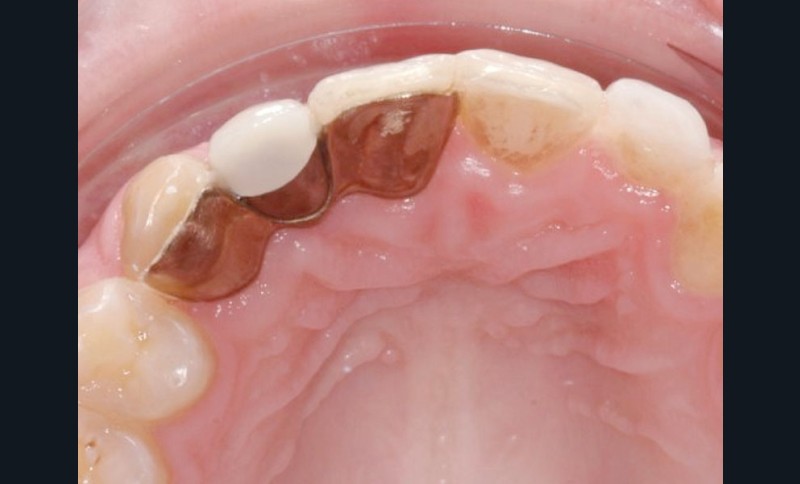

Différentes solutions thérapeutiques ont été utilisées au cours du temps pour compenser les édentements consécutifs aux agénésies d’incisives latérales. Les deux plus récentes sont les bridges collés et les implants. Les bridges collés ont fait leur apparition dans les années 1970. Plus élégante que le bridge conventionnel, cette option diminuait considérablement la mutilation des dents bordant l’édentement, une préparation minimale des faces linguales étant nécessaire. Malgré tout, dans les faits, la réalisation de ces bridges collés semble encore aujourd’hui, réservée à des experts de la prothèse conjointe (fig. 1).